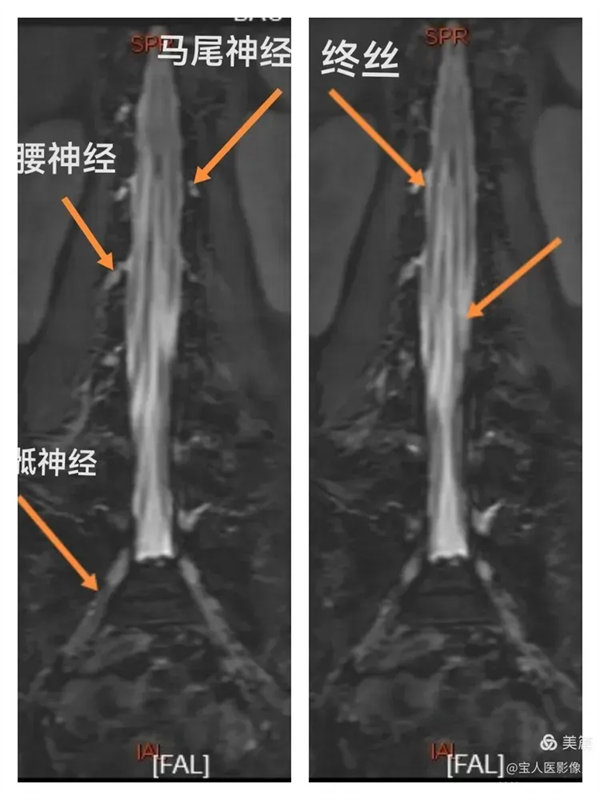

最大密度正面图,显示腰段脑脊液(高信号),其内的马尾神经以及腰神经(线状稍低信号)。

最大密度正面图,显示腰段硬膜囊内脑脊液(高信号),多条终丝、腰神经及骶神经(线状稍低信号)走行清晰。